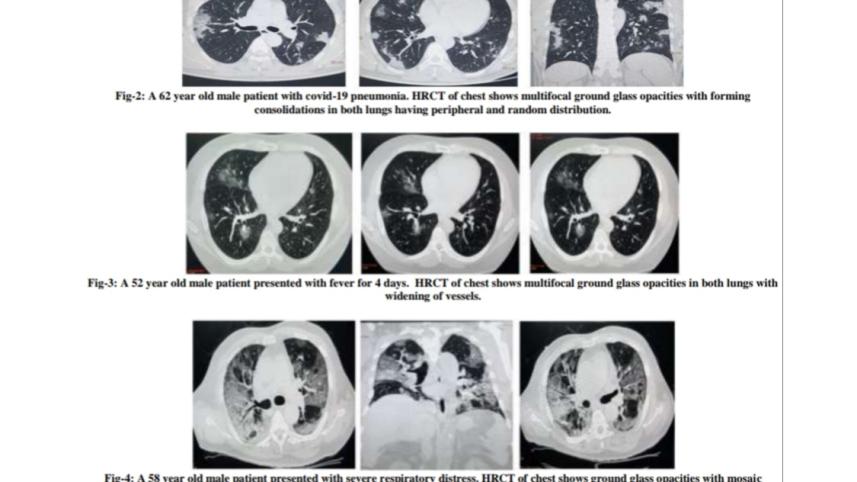

এই রোগীদের লক্ষণ ছিল জ্বর, কাশি ও বুক ব্যথা। প্রায় সবারই সিটি স্ক্যান পরীক্ষায় রোগের উপস্থিতি পাওয়া যায়। এসময় কারও কারও আরটি-পিসিআরের প্রথম নমুনা পরীক্ষার ফলাফল ‘নেগেটিভ’ এসেছে। কিন্তু তিন-চারদিন পরের নমুনা পরীক্ষার ফলাফল এসেছে ‘পজিটিভ’। এভাবে কোভিড লক্ষণ যুক্ত সন্দেহভাজন রোগীদের মধ্য থেকে ২১ জনের ‘পজিটিভ’ এবং ৩০ জনের ‘নেগেটিভ’ রিপোর্ট আসে।

এই গবেষণায় দেখা গেছে, সিটি স্ক্যানে সঠিক ফলাফলের সংবেদনশীলতা ৯৫ দশমিক ৪৫ শতাংশ এবং প্রথম নমুনায় আরটি-পিসিআরের সংবেদনশীলতা ৮৬ দশমিক ৩৬ শতাংশ।